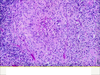

Histoplasmosis

Histoplasmosis

Histoplasmosis granuloma

Histoplasmosis